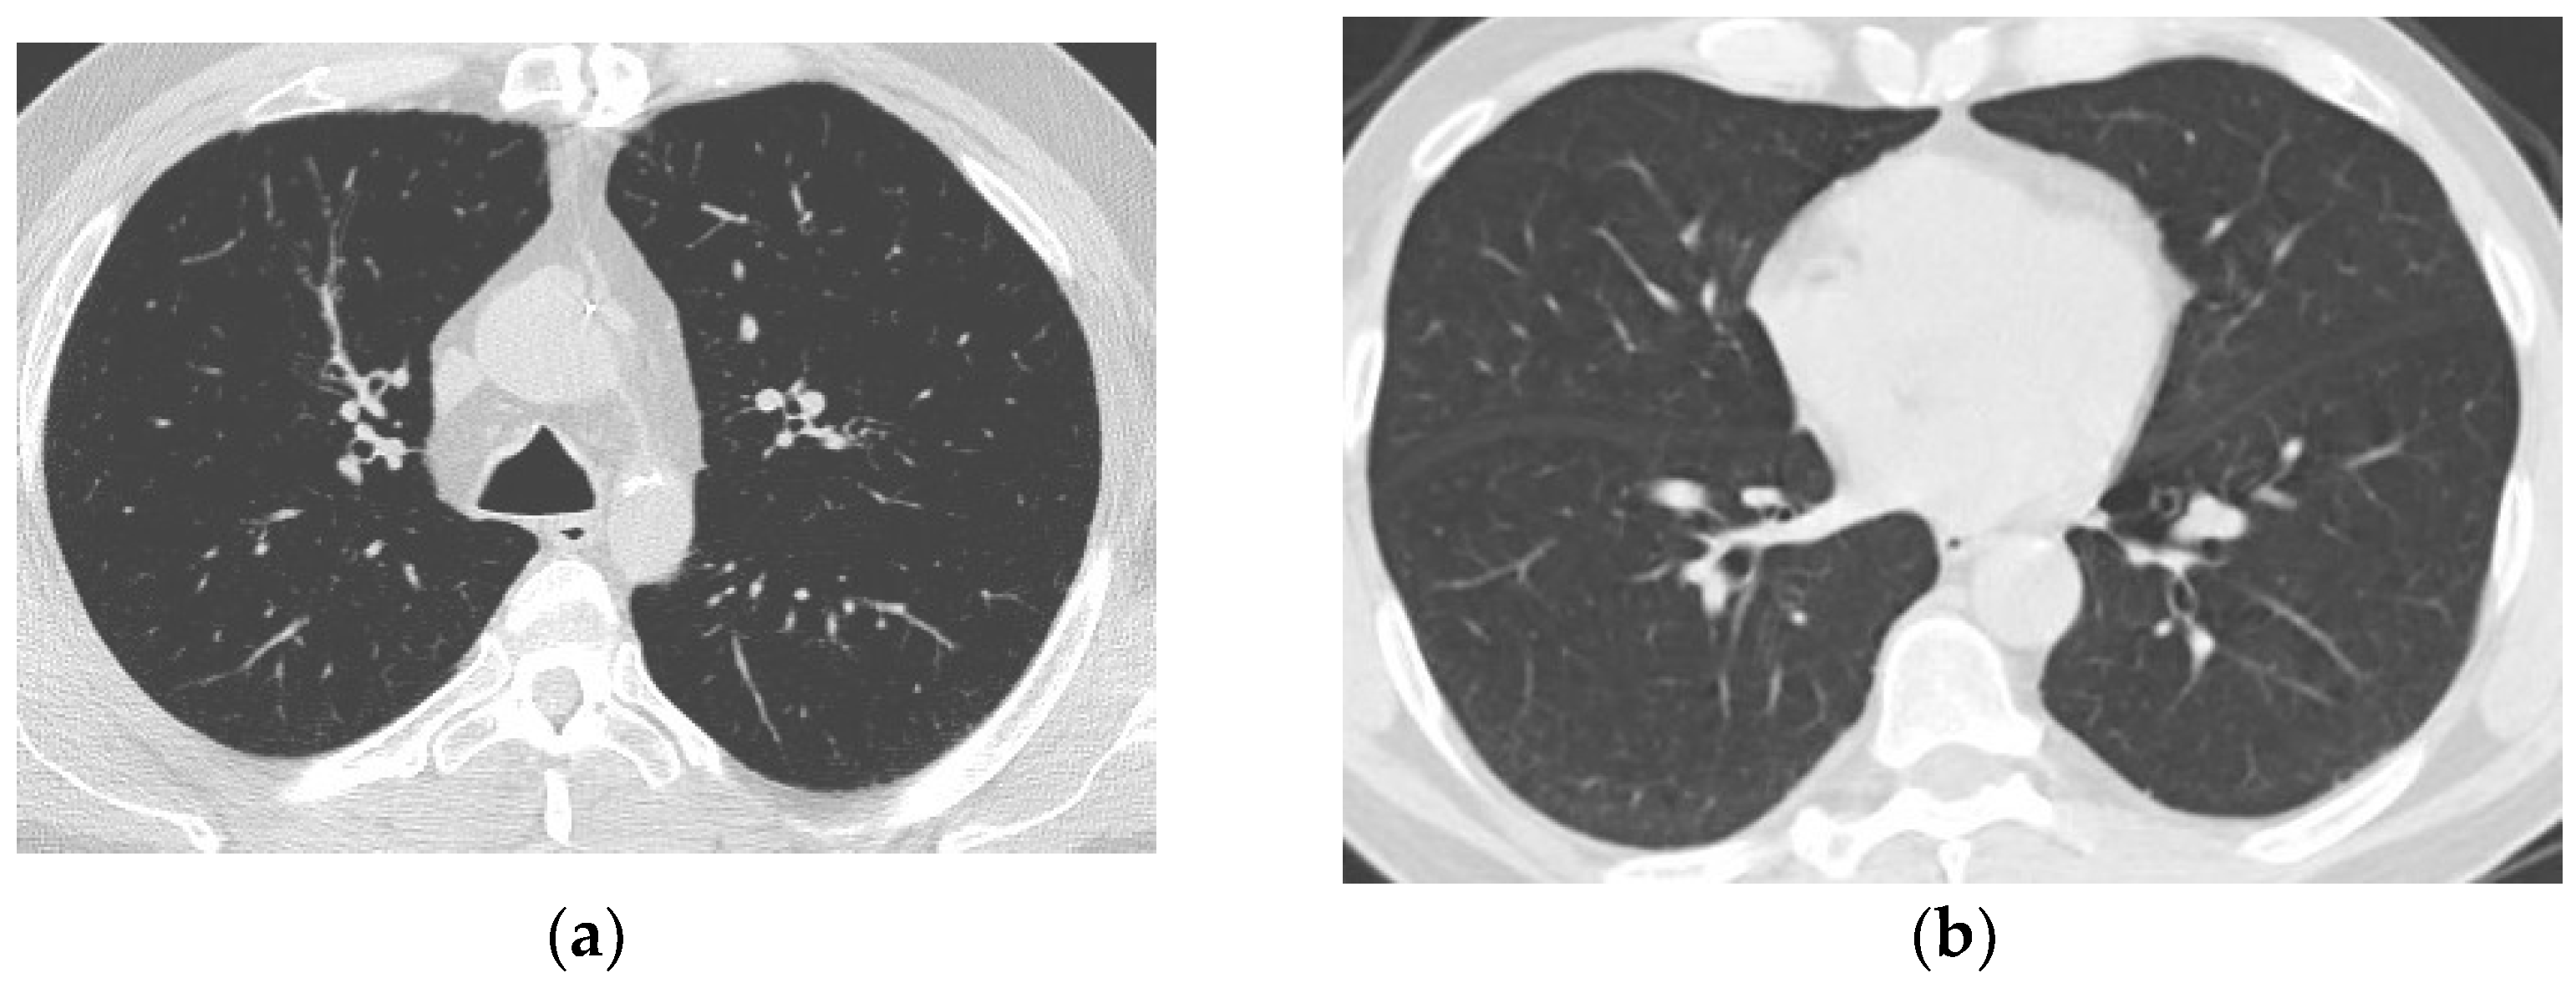

2.1. SARS-CoV-2 Ct-Scan Dataset